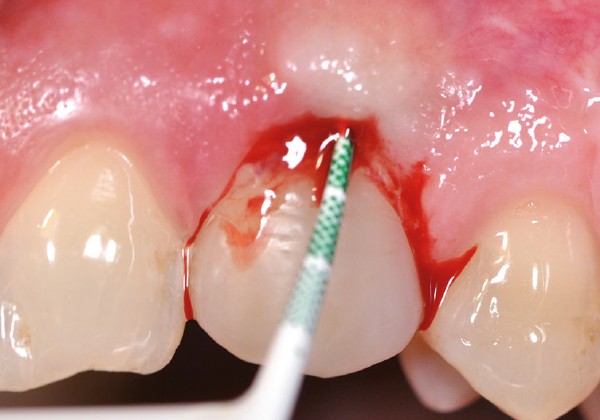

Les péri-implantites sont des maladies inflammatoires d’origine infectieuse qui se manifestent cliniquement par une inflammation des tissus mous, avec un saignement au sondage et/ou parfois une suppuration, ainsi qu’une perte d’attache et une profondeur de poche au sondage supérieure à 5 mm. Radiographiquement, cet état se manifeste par l’existence d’une perte osseuse, correspondant à une exposition de plusieurs spires de l’implant (fig. 1).